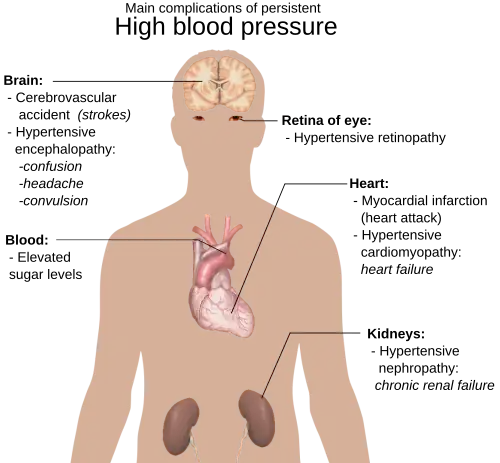

Hypertension, also known as "high blood pressure", is a long term medical condition in which the blood pressure in the arteries is persistently elevated.[64] High blood pressure usually does not cause symptoms.[65] Long term high blood pressure, however, is a major risk factor for coronary artery disease, stroke, heart failure, peripheral vascular disease, vision loss, and chronic kidney disease.[66][67]

Lifestyle factors can increase the risk of hypertension. These include excess salt in the diet, excess body weight, smoking, and alcohol consumption.[65][68] Hypertension can also be caused by other diseases, or occur as a side-effect of drugs.[69]

Lifestyle changes and medications can lower blood pressure and decrease the risk of health complications.[73] Lifestyle changes include weight loss, decreased salt intake, physical exercise, and a healthy diet.[68] If changes in lifestyle are insufficient, blood pressure medications may be used.[73] A regimen of up to three medications effectively controls blood pressure in 90% of people.[68] The treatment of moderate to severe high arterial blood pressure (defined as >160/100 mmHg) with medication is associated with an improved life expectancy and reduced morbidity.[74] The effect of treatment for blood pressure between 140/90 mmHg and 160/100 mmHg is less clear, with some studies finding benefits[75][76] while others do not.[77] High blood pressure affects between 16% and 37% of the population globally.[68] In 2010, hypertension was believed to have been a factor in 18% (9.4 million) deaths.[78]

Essential hypertension is the form of hypertension that by definition has no identifiable cause. It is the most common type of hypertension, affecting 95% of hypertensive patients,[79][80][81][82] it tends to be familial and is likely to be the consequence of an interaction between environmental and genetic factors. Prevalence of essential hypertension increases with age, and individuals with relatively high blood pressure at younger ages are at increased risk for the subsequent development of hypertension. Hypertension can increase the risk of cerebral, cardiac, and renal events.[83]

Complications of hypertension

Complications of hypertension are clinical outcomes that result from persistent elevation of blood pressure.[85] Hypertension is a risk factor for all clinical manifestations of atherosclerosis since it is a risk factor for atherosclerosis itself.[86][87][88][89][90] It is an independent predisposing factor for heart failure,[91][92] coronary artery disease,[93][94] stroke,[85] renal disease,[95][96][97] and peripheral arterial disease.[98][99] It is the most important risk factor for cardiovascular morbidity and mortality, in industrialized countries.[100]